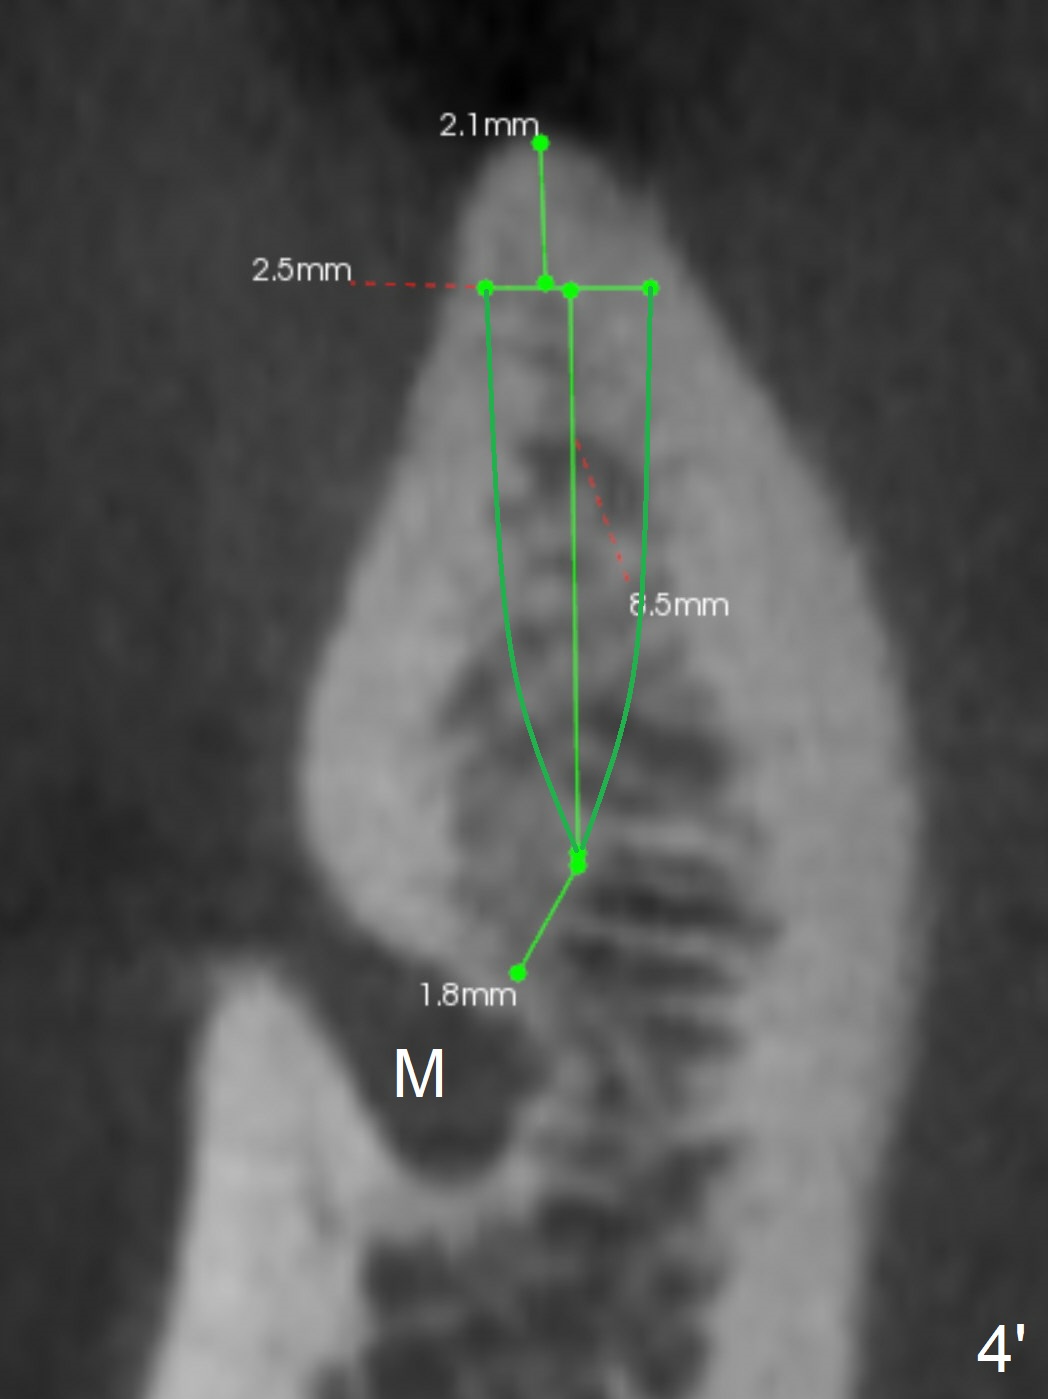

The ridge at #29 is not only narrow, but also short. It seems appropriate to place a short 1-piece implant (Fig.4 (Oblique Slicing), 4' (Curved Slicing)). B: buccal; M: Mental Nerve.